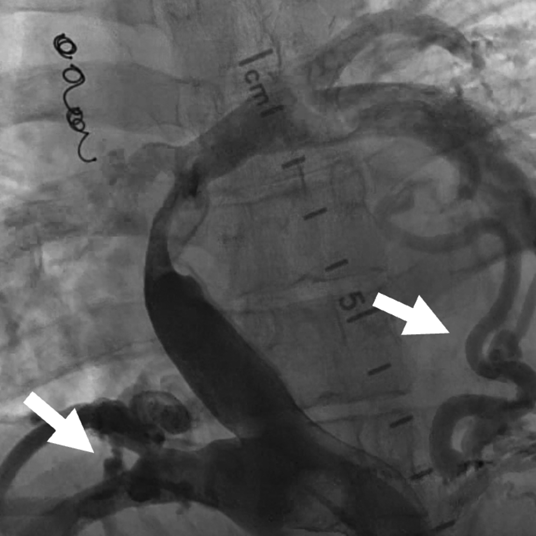

肺動脈閉鎖症,無脾症の診断で月齢3に左BTシャント変法を施行された.シャント閉塞認め,1歳3か月時に左BTシャント変法を,2歳時に右BTシャント変法を追加された.3歳時に両方向性グレン手術施行し,5歳時に心外導管型フォンタン手術(ePTFE 18 mm)施行した.術直後の心臓カテーテル検査から心外導管に造影欠損部を認めており,2 mmHgの圧較差を認めていた(Fig. 5). 17歳時の心臓カテーテル検査では,心外導管の圧較差2 mmHgと狭窄の進行はなく,下大静脈圧は14 mmHgで再手術の適応はないと判断されていた.17歳ごろより1年間ワーファリンを自己中断していた.その後当院成人先天性心疾患外来紹介.19歳時より倦怠感,下血,喀血が出現し,心臓カテーテル検査を施行した.下大静脈圧は26 mmHg,平均肺動脈圧は8 mmHgと圧較差を14 mmHg認めた(Fig. 6),心外導管に対してバルーン拡張術を施行し,下大静脈圧は20 mmHgと軽度改善したが下大静脈圧の十分な低下は得られず,手術適応と考えられ,再心外導管置換目的に当科入院となった.

Pediatric Cardiology and Cardiac Surgery 36(1): 84-89 (2020)

Fig. 5 Angiography 4 years after Fontan completion showing an inflection in the conduit in patient 2

Fig. 6 Preoperative angiography showing severe stenosis and a high number of collateral vessels in patient 2